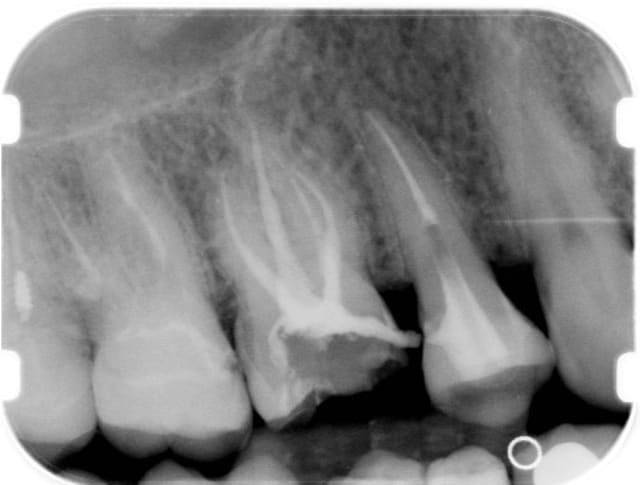

08/11/2008 à 14h14

Et celle là elle est pas belle???

Une heure, je trouve le 4ème canal,je le cathétérise jusqu'au bout, je me dis ça démarre bien, on y va tranquille, digue, edta hypo par litres etc etc.

ET?????

Le dernier instrument (heureusement le dernier!!), il pète dans le canal MV2.

AGGRRRRRRRRRRRRRRRRRRRRRRRRRRRRRRRRRR LES BOULES !!!!!!!!

J'en ai marre, je les vérifie à la loupe, je ne force pas, et de temps en temps j'en casse.

Et comme je ne dois pas être très doué j'arrive à passer à côté une fois sur mille.

J'ai envie d'essayer un autre système FKG, qui a l'air bien, je l'ai acheté il y a six mois, pas eu le temps de mettre en pratique.

Pour ce qui est du prix, quand je dévitalise, c'est que la dent a une énorme carie et donc, sauf exception, c'est couronne, donc le prix de l'endo je m'en fous, c'est pour moi un acte global, je fais l'empreinte dans la même séance de 2 heures.

Mais bon quand tu sens que tu vas te faire une belle endo et que ça se finit comme ça , ça te fout un peu ta journée en l'air.

Ce qui me gonfle aussi c'est que je n'arrive pas à joindre ma radio, il y a un post là dessus, j'y vais voir et je reviens.

Dsc 0022 zyz4bz - Eugenol

Fred

08/11/2008 à 15h45

Ca marche!!!